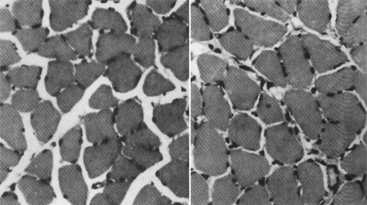

Muscular force is in proportion to the physiologic cross-sectional area.36 The physiologic cross-sectional area is a function of the number of contractile elements in the muscle (Figure 2-9). Muscle will atrophy, or lose contractile elements, when it is not routinely required to develop other than minimal tension. Conversely, the muscle cells hypertrophy when routinely required to develop large amounts of tension, as long as the tension demands are within the physiologic limit of its adaptive response. The change in size (circumference) of a muscle occurs either by a decrease in sarcomeres (atrophy) (Figure 2-10) or an increase in sarcomeres (hypertrophy) (Figure 2-11). In hypertrophy the addition of sarcomeres in parallel is accompanied by the addition of sarcomeres in series, though to a lesser extent than those added in parallel.

Figure 2-10 Atrophy of muscle. Micrographs from normal muscles (top panel). Micrographs from immobilized muscles illustrating atrophied muscles where the sarcomeres have decreased in diameter (bottom panel). (From Leiber RL et al: Differential response of the dog quadriceps muscle to external skeletal fixation of the knee, Muscle Nerve 11:193, 1988.)

Figure 2-11 Hypertrophy of muscle. Cross-section of control rat soleus muscle (left). Cross-section of hypertrophied rat soleus muscle (right). (From Goldberg AL et al: Mechanism of work-induced hypertrophy of skeletal muscle, Med Sci Sports 3:185, 1975.)